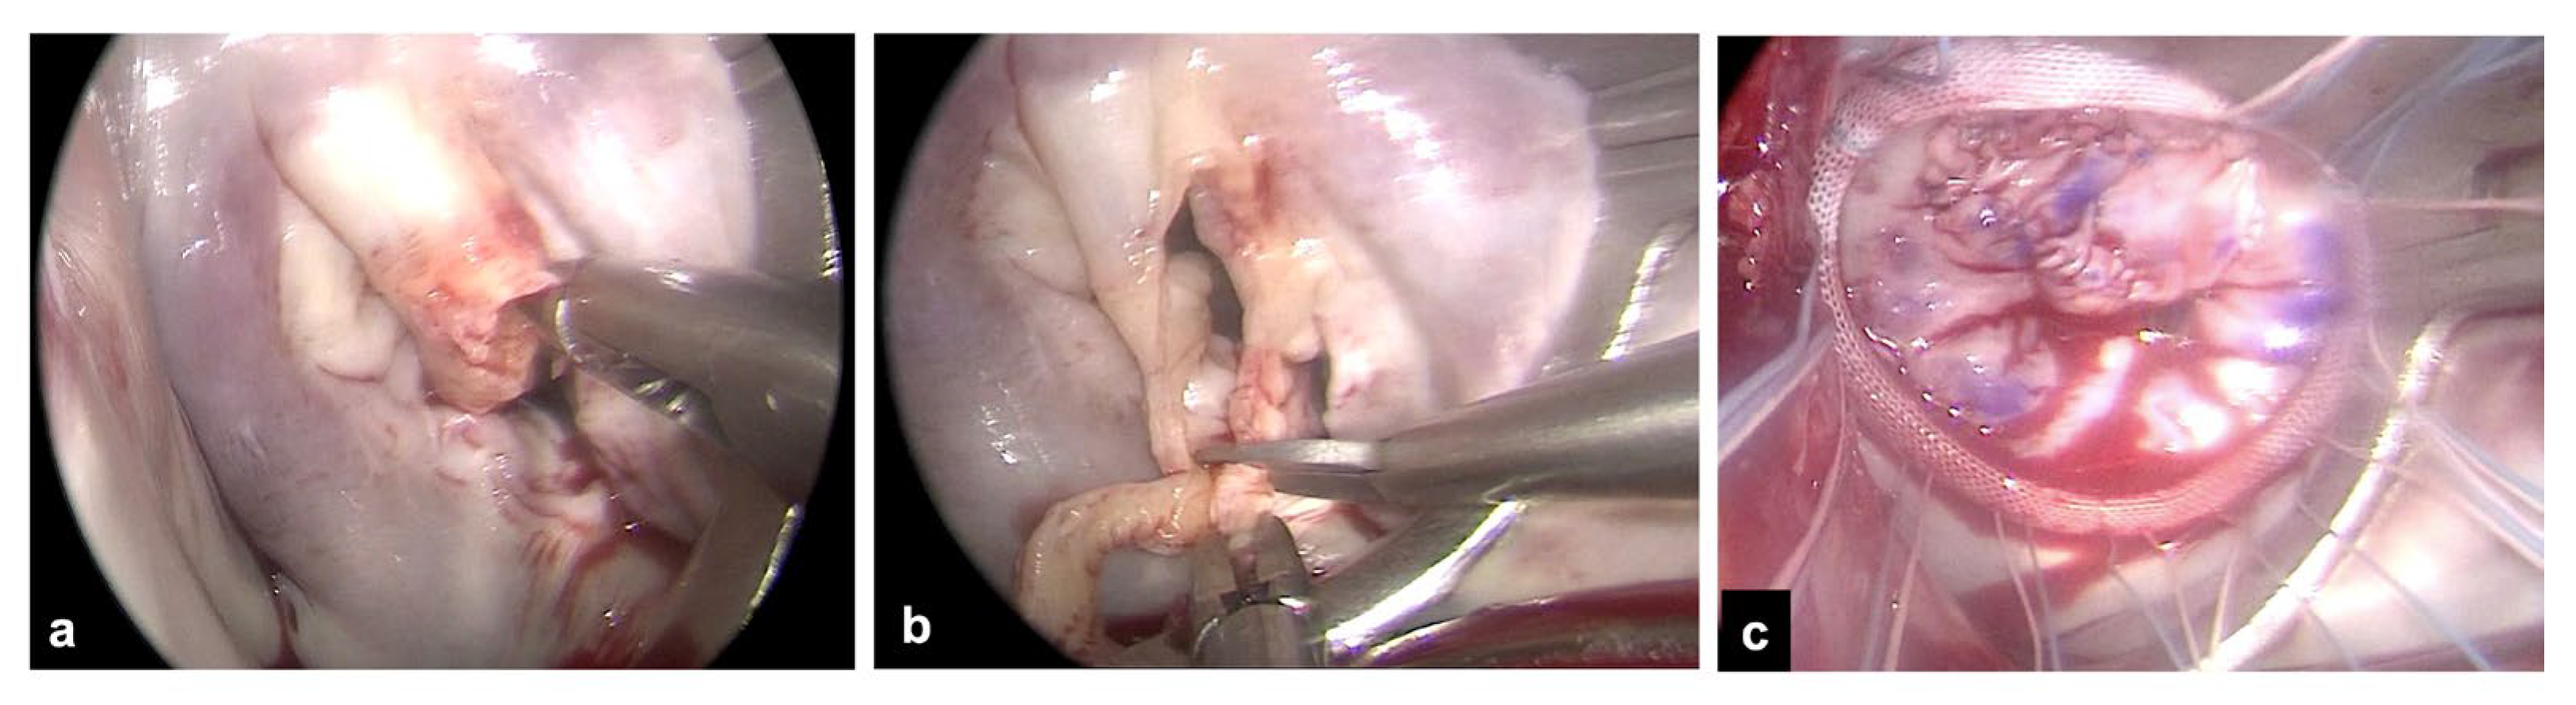

Figure 1. Exposure of the mitral valve through a right mini-thoracotomy and endoscopic view. a. Example of a large vegetation on scallop A2 with leaflet perforation. b. Extensive resection of the anterior leaflet around the infected tissue. c. Mitral valve repair with patch on the anterior leaflet and ring annuloplasty.

The right mini-thoracotomy approach, perfusion strategies and aortic clamping techniques used for patients undergoing MV surgery have been described previously Figure 1 [9,10,12–15]. Briefly, a right anterolateral mini-thoracotomy in the fourth intercostal space is performed and double lumen endotracheal tube intubation for the single left lung ventilation is provided in all patients. More posteriorly, a secondary port is prepared for the endoscope and for carbon dioxide insufflation. An additional sixth intercostal space port is created for pump suction. After the institution of cardiopulmonary bypass, core temperature is lowered to 30 °C. Arterial perfusion is gained with a peripheral femoral or axillary cannulation. The latter is usually preferred to provide antegrade systemic perfusion in the case of severe atherosclerotic burden [12]. Venous drainage is obtained via double femoral and jugular cannulation. All cannulae are inserted with a Seldinger technique, either under direct vision in case of vascular surgical exposure or percutaneously. The ascending aorta is clamped using the endoaortic balloon or a trans-thoracic clamp. In the endoaortic clamping setting, aortic occlusion and cardioplegia delivery are gained with a balloon catheter inserted through the sidearm of a femoral arterial cannula (21F or 23F Intraclude®, Edwards Lifesciences, Irvine, CA, USA). In the trans-thoracic clamping setting the clamp is addressed towards the ascending aorta through the first intercostal space with a Chitwood clamp or through the main port with a Cygnet® flexible clamp. Cardioplegia is delivered with a 7F cardioplegia needle (CalMed Technologies, Santa Inez, CA, USA) placed into the proximal ascending aorta. Antegrade myocardial protection is provided with St. Thomas (PlegisolTM, Hospira Inc., Lake Forest, IL, USA) or Custodiol (Bretschneider histidine, tryptophan, ketoglutarate solution, Köhler Chemie, Bensheim, Germany) cold crystalloid cardioplegia [14]. Superior and inferior vena cava snaring is obtained by placing tourniquets around the vessels or by placing endovascular balloons to provide a temporary mini right atriotomy to drain the cardioplegic solution and in patients requiring associated right atrial procedures, most commonly tricuspid valve repair. The MV is exposed through a standard left atriotomy, parallel and posterior to the interatrial septum. The extension of vegetations, leaflet involvement and the chances of valve repair are assessed. Clamp release is obtained at a core temperature above 33 ◦C during rewarming. Intraoperative transesophageal echocardiography is mandatory and was used in all patients to guide the correct positioning of the cannulae before the onset of cardiopulmonary bypass and to assess cardiac function, residual MV regurgitation in case of MV repair, paravalvular leaks, and prosthetic valve gradients after the intracardiac phase of the operation.